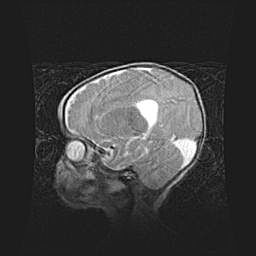

Подострая гематома правой гемисферы мозжечка.

Наружная гидроцефалия.

Возраст: 15 дней

Вес: 3100 г

Пол: женский

Окружность головы: 37 см

Срок гестации: 35-36 недель

При открытой наружной форме гидроцефалии у новорожденных расширяются и переполняются субарахноидные пространства.

Кровоизлияния в мозжечок имеют две клинико-анатомические формы: полушарные гематомы и кровоизлияния в червь.

К появлению этой патологии может привести: повреждения головного мозга, возникающие в результате асфиксии и гипоксии плода при беременности, или травмы во время родов. Редко гематома мозжечка может быть результатом первичной коагулопатии и сосудистой мальформации, диссеминированном внутрисосудистом свертывании, изоиммунной тромбоцитопении.